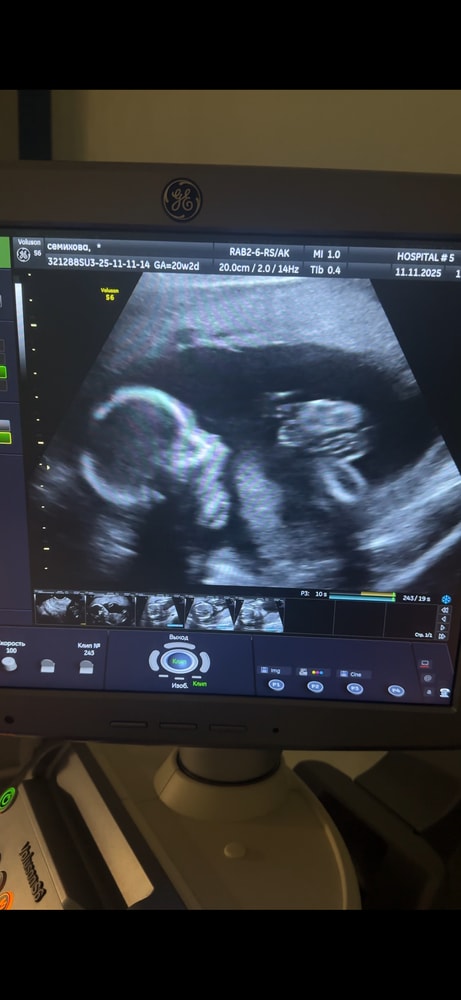

2 скрининг 11.11 ✨😇

также на 3 дня меньше , чем по мес.

сказали, что это в пределах нормы )

развиваемся согласно срокам шейка 35мм 👌🏻🤗